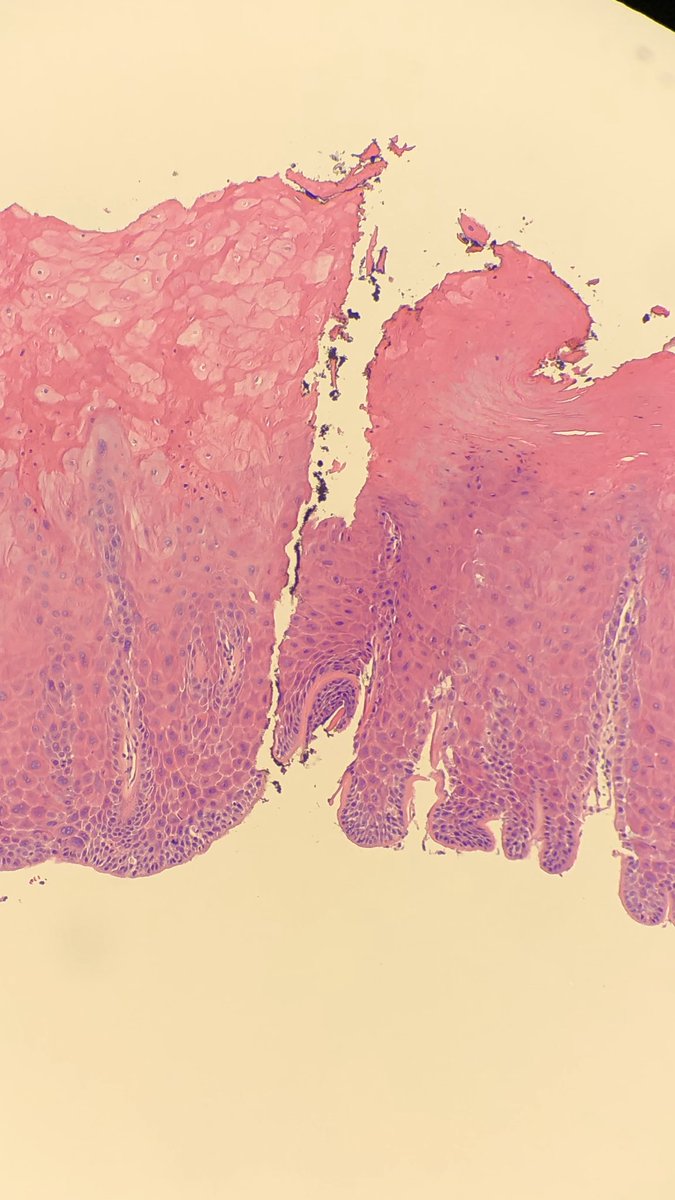

Granular cell tumor (GCT): can induce marked pseudoepitheliomatous hyperplasia (especially on the tongue) which can lead to misdiagnosis as a squamous cell carcinoma

#dermpath#pathology#dermatologypic.twitter.com/GhZUa8ErFs

Prikaži ovu nit -

Curious to see what you would call this “tongue lesion” in a 50-year-old man?

@Chucktowndoc@PathDocBoston@ENTpathology@ktmontone@LisaRooperMD@NRiddleMD@lfwalkerlw@Ben_WolfPath#pathology#surgpath#entpathpic.twitter.com/rJTUpRqXYD